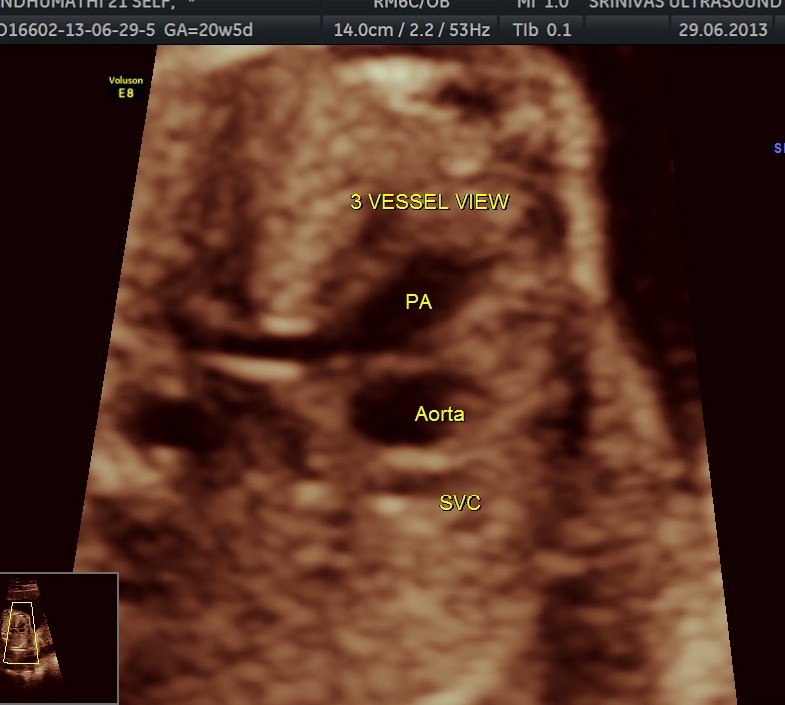

The following pictures are of the 20 weeks gestation.

The following are of the 26 weeks gestation.

The following are of the 34 weeks gestation :

The following are from the 37 weeks scan.